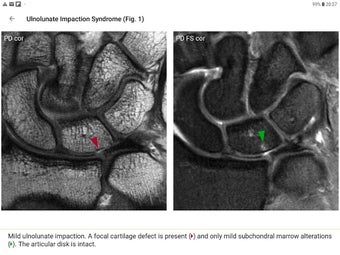

Die Pro-Version enthält mehr als 4.000 hochwertige Bilder von herausragender Bildqualität, die den Text veranschaulichen. Sie sind so konzipiert, dass sie dem Leser einen schnellen Überblick über die wichtigsten Informationen zum Zustand geben.